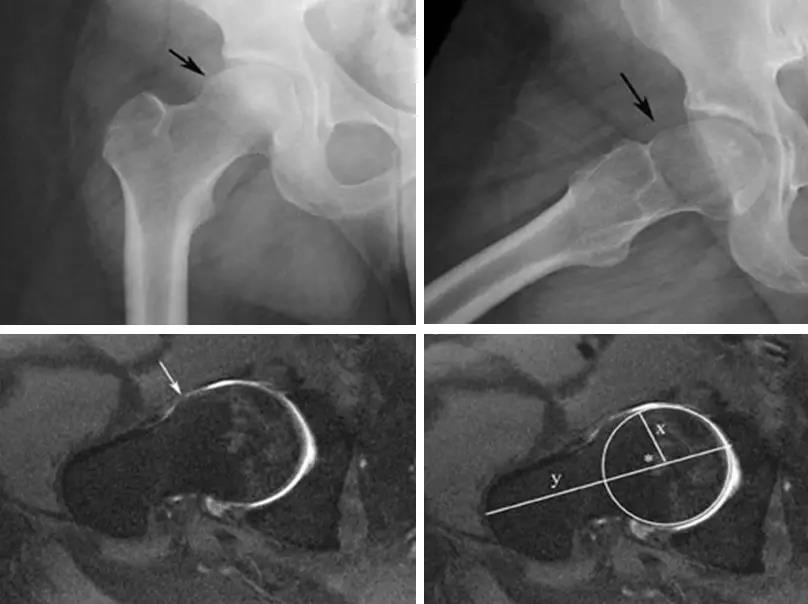

- 股骨头中心O点为圆心,股骨头正常最大半径为r,从股骨头颈连接处骨质与这个圆的交点(A点)到股骨头中心点作直线OA,此直线与股骨颈中轴线OB的交角为α角。

- 反映股骨颈骨赘突出程度,α角越大,越容易发生前上方股骨头颈与髋臼唇的撞击。

- FAI组中该角平均为74.0°±5.4°,正常对照组为42.0°±2.2°。

- α角>50°是诊断FAI的临界值。

- 股骨头颈联合处前上缘骨性突起。

- 凸轮撞击型FAI--并盂唇撕裂。